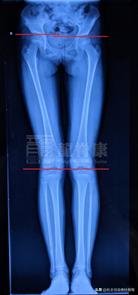

双下肢全长片检查

因此诊断患儿是青少年特发性脊柱侧弯伴真性长短腿 。我的诊断依据是:根据患儿的全脊柱X光测量出Cobb角约为26°,而且左侧腰部肌肉隆起ATR约9°,无其他特殊病史及体表检查,可排除是由其他疾病引起的,故诊断为青少年特发性脊柱侧弯。另外,从双下肢全长片可见,患儿右下肢股骨明显较左侧长,是真性的长短脚。

2、患儿有真性长短脚,右长左短,影响到骨盆两侧高低不等,右高于左。骨盆是脊柱的 根基 ,若 骨盆高低不等 是会令脊柱有侧弯生长的趋势。这种情况下必须通过鞋垫来调整平衡双下肢的长度,以减小骨盆高低不等对脊柱侧弯发展的影响。